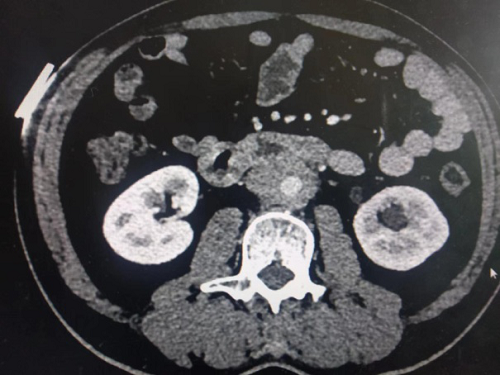

辅助检查:完善泌尿系CTU示腹主动脉下段、双侧髂总动脉周围见软组织影环绕,可见延迟强化,于左侧髂总动脉水平病变与左输尿管分界不清,相应水平左输尿管狭窄,以上输尿管,肾盂、肾盏扩张积水,腹腔、腹膜后未见明显肿大淋巴结。(如下图1-4)

(图1-4泌尿系CTU示考虑腹膜后纤维化累及左输尿管致尿路梗阻)